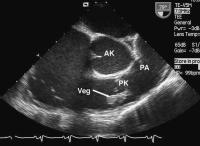

Abbildung 5: Transösophageales Echo: destruierte Pulmonalklappe (PK) und entzündliche Vegetation (Veg) an der Pulmonalklappe; RV = rechter Ventrikel, AK = Aortenklappe, PA = Pulmonalarterie

Keywords: EchokardiogrammEchokardiographieEndokarditisHerzKardiologiePulmonalklappetransösophageal